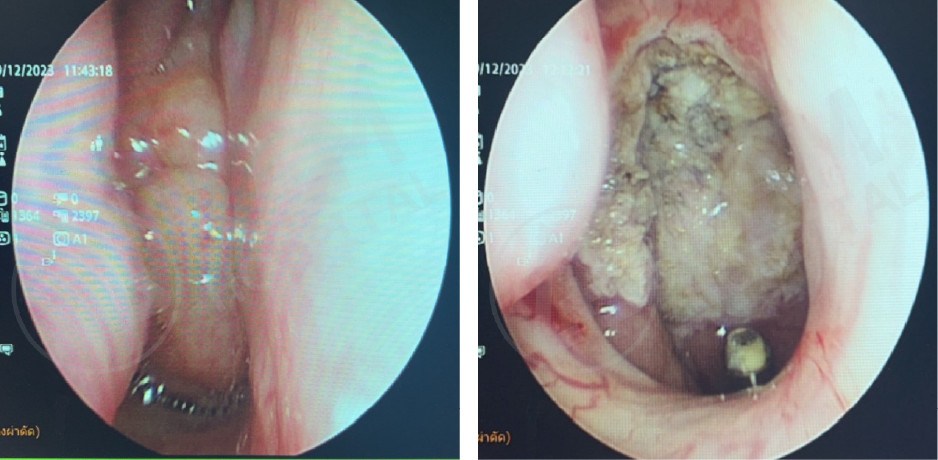

通过口腔内镜检查精准定位气道阻塞部位,并针对性地实施微创手术,以达到最佳治疗效果和最小创伤,核心技术包括:包括软腭手术联合颈部肌肉缝合收紧手术、借助口腔内镜缩小舌根的手术。

通过口腔内镜辅助,对舌根和会厌部位的肿瘤进行微创手术

通过口腔内镜辅助,对喉部或声带部位的肿瘤进行不用刀的微创手术。

术前 |

术后 |

术后

Source: Photo courtesy of Dr. Puripan Aramawattanapong, Ear, Nose, and Throat Specialist